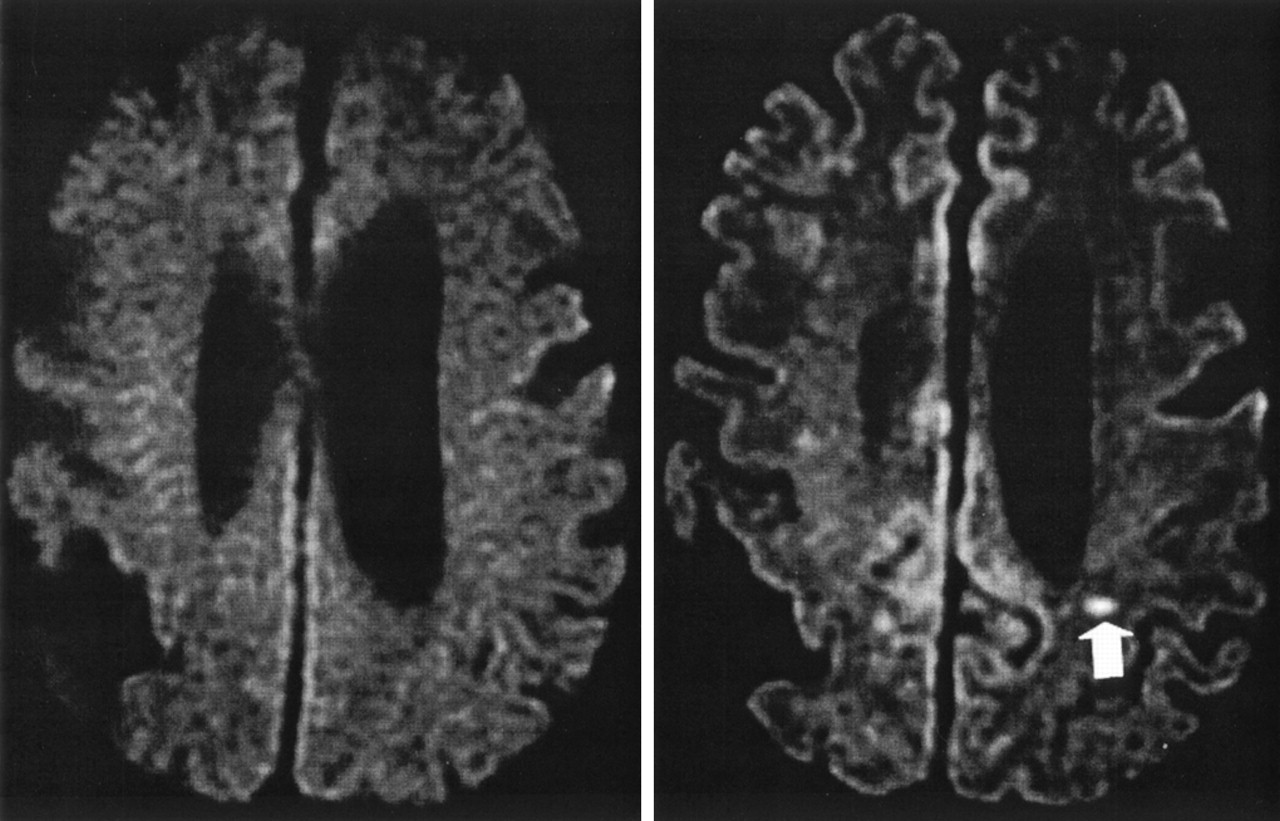

Inatomi et al .,在未来的研究中,进行MRI /醉酒驾车在14天内129例TIA发作。一个多元逻辑回归模型表明,长期TIA的持续时间和更高的脑功能障碍是独立的因素与驾车异常。

社论的作者Warach现在Kidwell指出,许多研究表明,近一半的患者临床TIA醉酒驾车异常。曾经被认为是一个有意义的区别基于持续时间的赤字和隐含一种良性病程和预后是现在公认的一部分的急性脑血管疾病和紧急。推荐的TIA的诊断检查和管理是脑梗死的区别。图